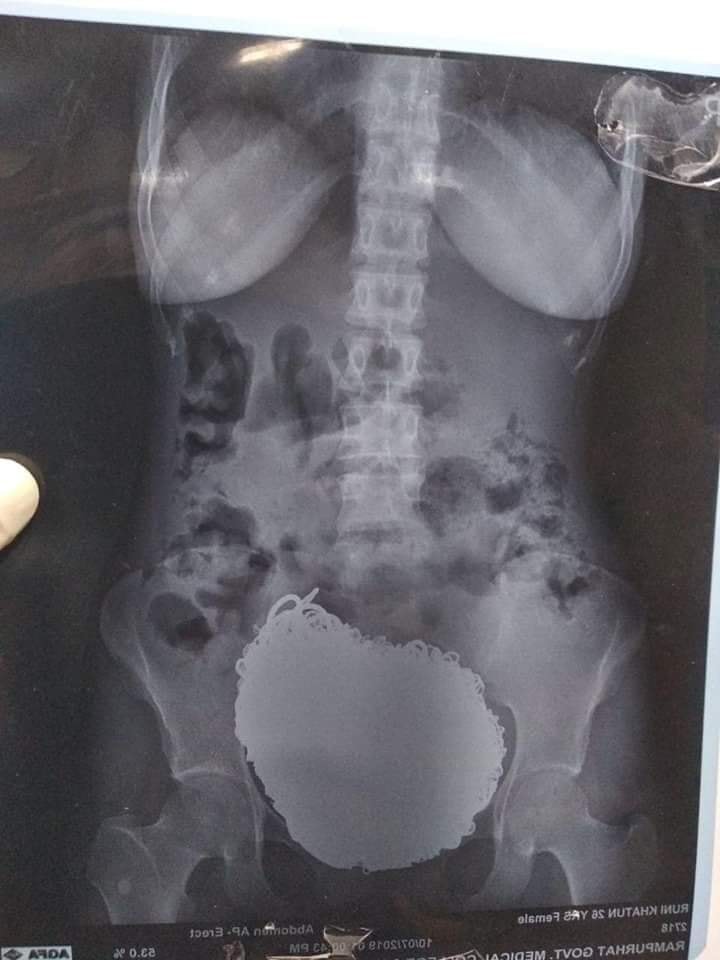

Doctors at the Rampurhat Government Medical College and Hospital ran several tests on the woman over the course of a week. X-rays eventually revealed the source of her discomfort: a softball-sized lump of coins, necklaces, anklets, rings, earrings and watches nestled in her stomach.

“They were so heavy that they came down to her pelvis,” he said.

Her age is listed at 26 on an X-ray, but Reuters reports that she is 49. As of this writing, Global News has been unable to confirm the woman’s exact age.

A mass of coins is shown inside a woman’s stomach at Rampurhat Government Medical College and Hospital in India. Department of Memelogy, MAMC/Facebook